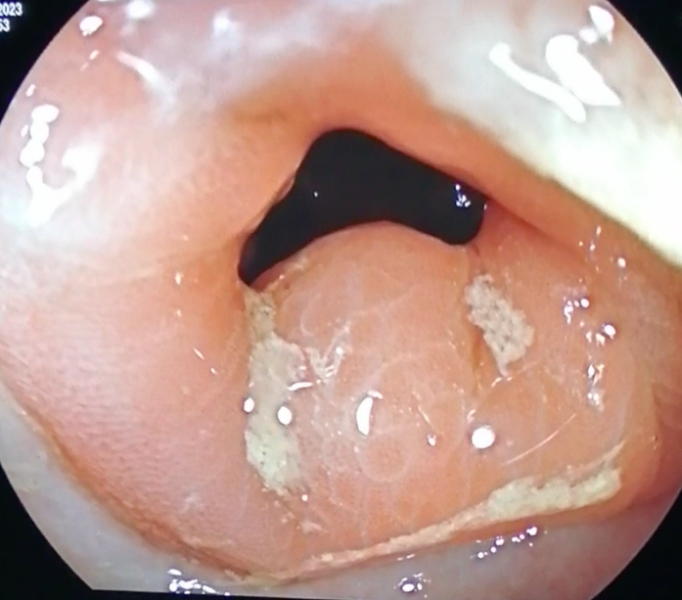

(Un)desired guest in a Peutz-Jeghers syndrome Patient's Capsule Endoscopy

Fotografia